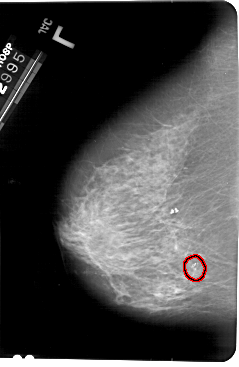

A_1496_1.RIGHT_CC

RIGHT_CC LINES 5386 PIXELS_PER_LINE 3196 BITS_PER_PIXEL 12 RESOLUTION 43.5 NON_OVERLAY